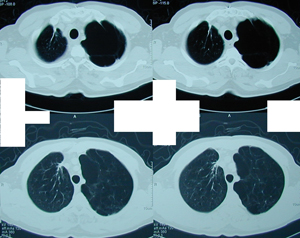

Εικόνα 3 α-ε

Αξονική τομογραφία του θώρακος. Διακρίνεται η παρουσία μεγάλου πνευμοθώρακος παρά την ύπαρξη της παροχέτευσης και την σύνδεση της συσκευής Bullau με συνεχή αρνητική πίεση. Επίσης υπάρχουν πολλαπλές μεγάλες εμφυσηματικές φυσαλίδες αμφοτερόπλευρα. Επιπλέον υπάρχει εκτεταμένο υποδόριο εμφύσημα.